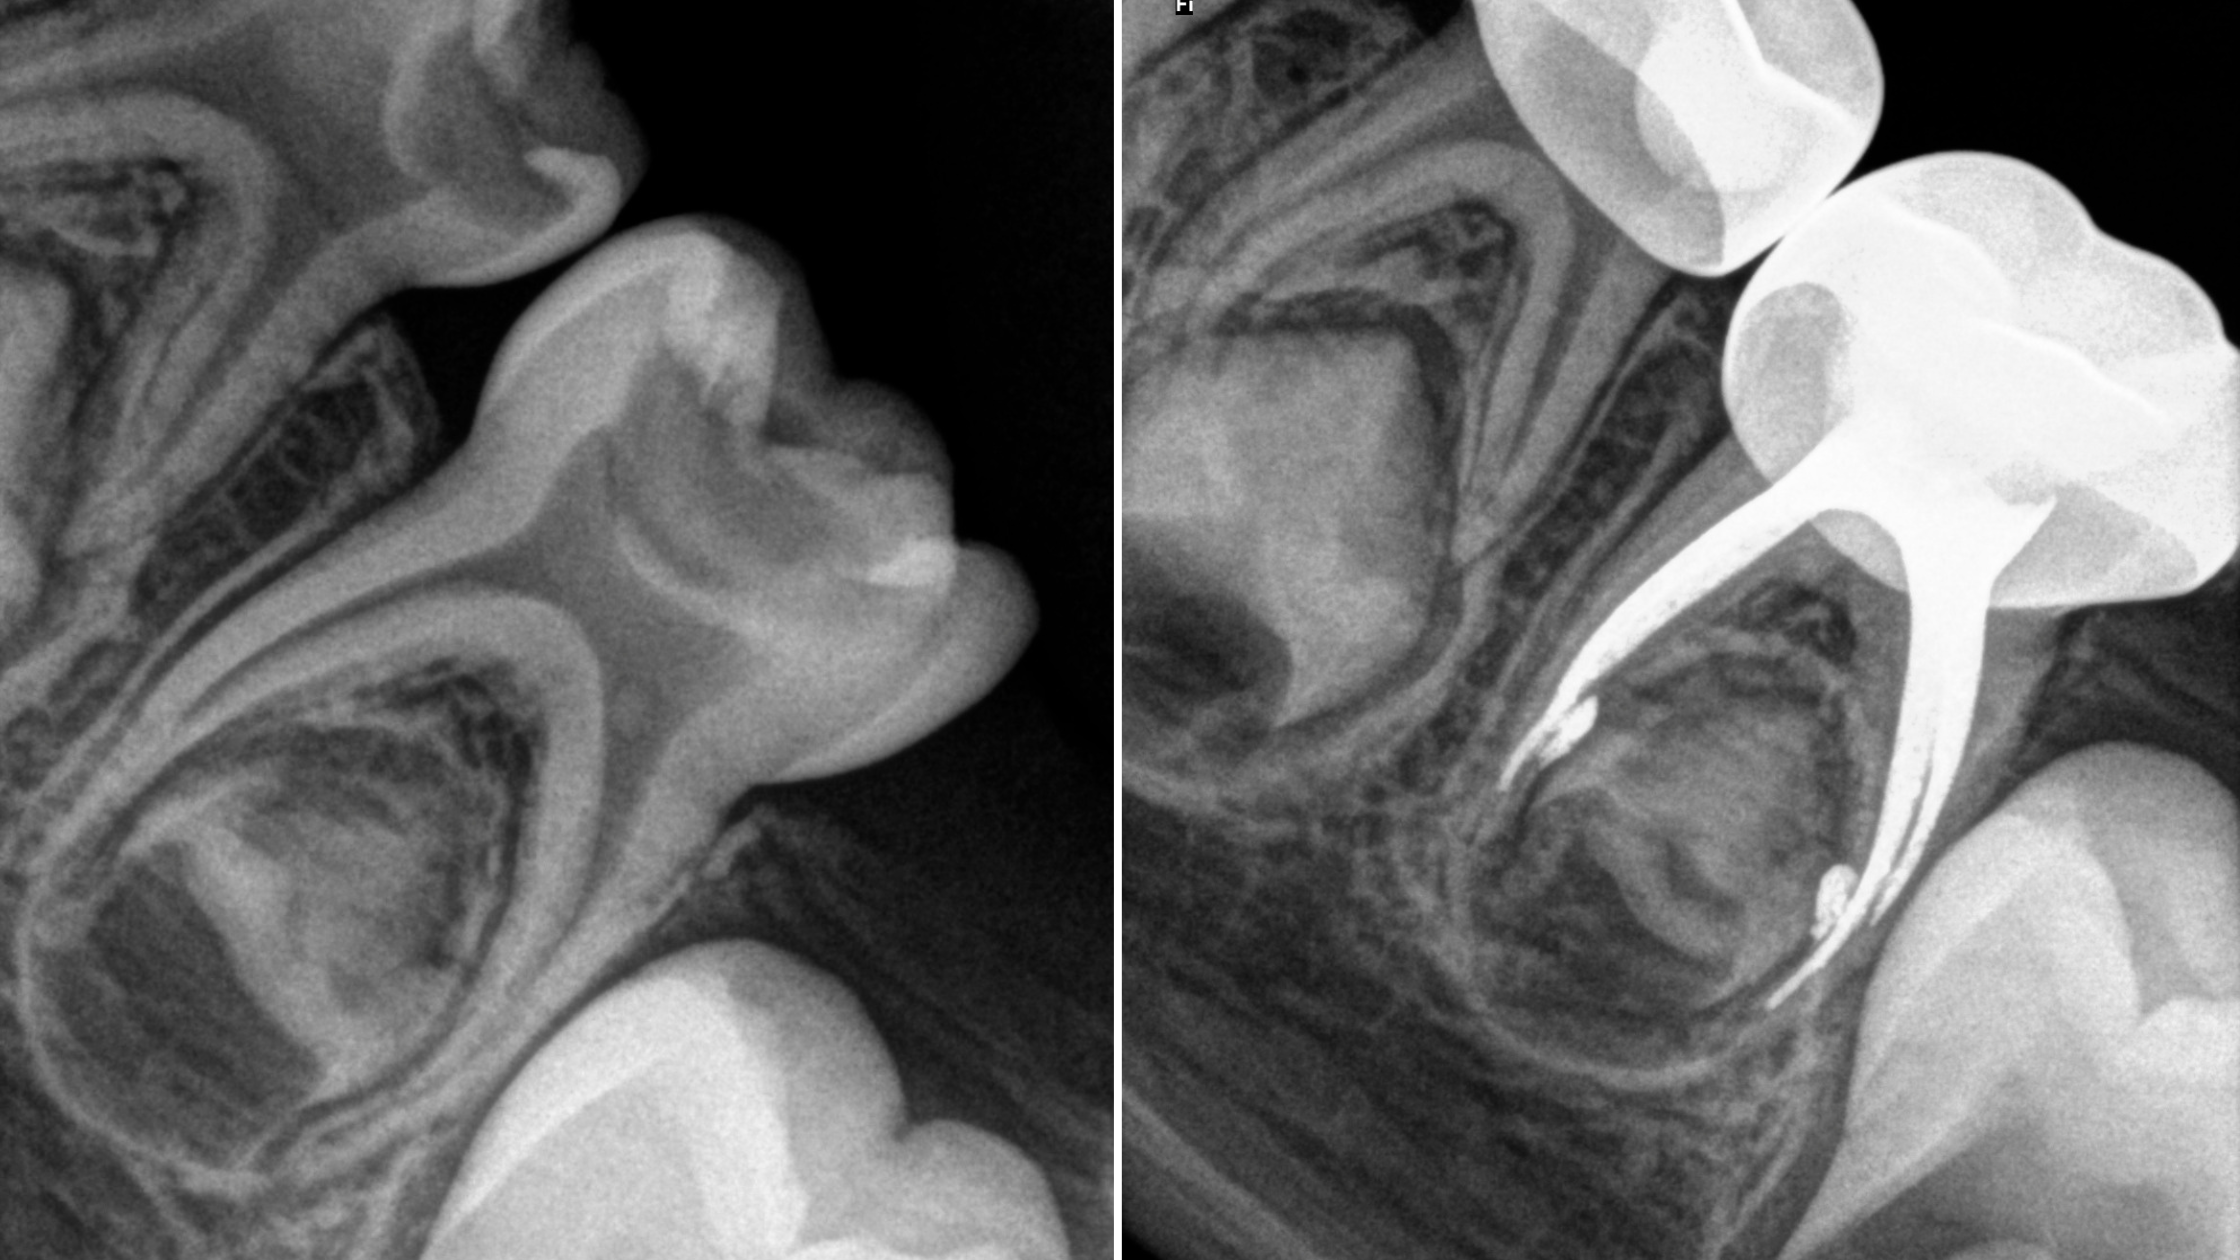

Diagnostyka radiologiczna w pedodoncji

• technika wykonywania zdjęć RTG u dzieci - zasady i unikanie błędów

• różnicowanie obrazu patologii i artefaktów diagnostycznych

• ocena resorpcji, zębów w fazie wymiany i zmian okołowierzchołkowych

• radiologiczne kryteria decyzji: leczyć, usuwać czy obserwować

• analiza przypadków i zdjęć RVG: wskazania, przebieg, efekty leczenia

Quiz radiologiczny

• planowanie leczenia krok po kroku na podstawie zdjęć radiologicznych

• ocena RTG i plan leczenia krok po kroku